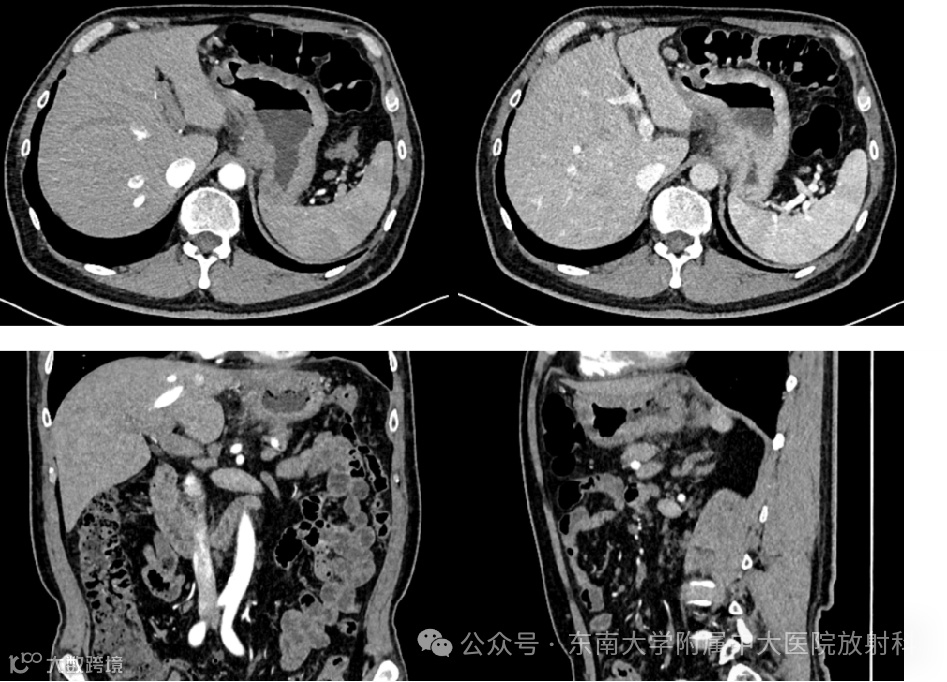

病例3

男,64岁

主诉:上中腹痛1年,加重1月

现病史:患者1年前出现上中腹部疼痛,饮酒后和饥饿时明显;1月前患者腹痛加重,进食后减轻,不伴腰背部放射痛,伴恶心呕吐,呕吐物为少量胃内容物。无发热寒战、无恶心呕吐、无呕血黑便,无胸闷胸痛,无腹胀。查胃镜提示:1.胃角溃疡(性质待定)2.慢性胃炎急性活动;黏膜活检标本(胃角溃疡):低分化腺癌。现患者为求进一步诊治至我科门诊,门诊拟“胃小弯恶性肿瘤”收住入院。病程中,患者神志清,精神可,食欲可,睡眠可,小便正常,近5年大便次数增加,3-4次/天,伴大便不成形,近期体重无明显改变

影像学检查